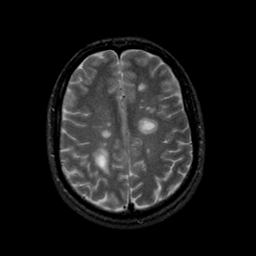

MR Study #9, April 14, 1991 -- Slice #35